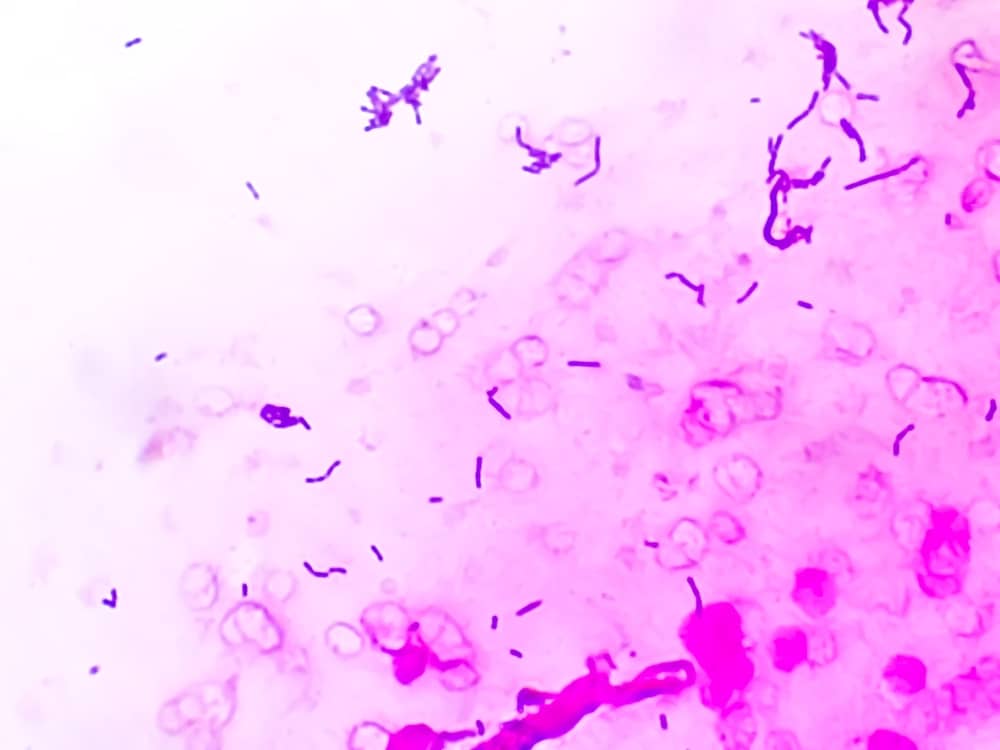

Phương pháp nhuộm Gram là kỹ thuậ nhuộm vi sinh. Giải pháp này giúp phân biệt vi khuẩn thành hai nhóm chính: Đó chính là vi khuẩn Gram dương và vi khuẩn Gram âm, dựa trên chính khả năng giữ màu của thành tế bào sau khi nhuộm.

Nhờ vào đặc điểm của vi khuẩn Gram dương có thành tế bào dày, giữ màu tím của thuốc nhuộm crystal violet, trong khi đó vi khuẩn Gram âm lại có thành tế bào mỏng, mất màu tím và chuyển sang màu hồng khi nhuộm với thuốc đối chiếu safranin.

- Đặt lam kính dưới kính hiển vi với vật kính dầu (100x) để quan sát. Vi khuẩn Gram dương sẽ có màu tím, trong khi vi khuẩn Gram âm có màu hồng.